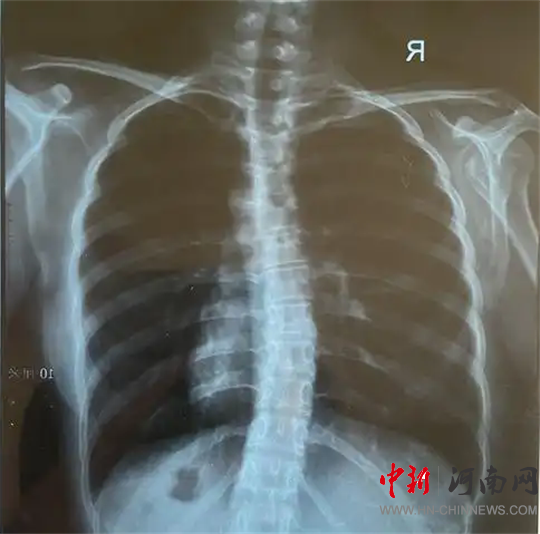

檢查結果為

脊柱側彎!

脊柱側彎,又稱脊柱側凸,是指脊柱偏離正中位置,身體向一側彎曲的骨骼畸形。

脊柱側彎絕大部分發(fā)生在青少年時期,是嚴重危及青少年群體身心健康的常見疾病,具有發(fā)病率高、起病隱匿等特點,發(fā)病高峰集中在10-14歲。

脊柱側彎可分為特發(fā)性脊柱側彎和姿勢性脊柱側彎等多種類型,特發(fā)性脊柱側彎是青少年最常見的側彎類型。